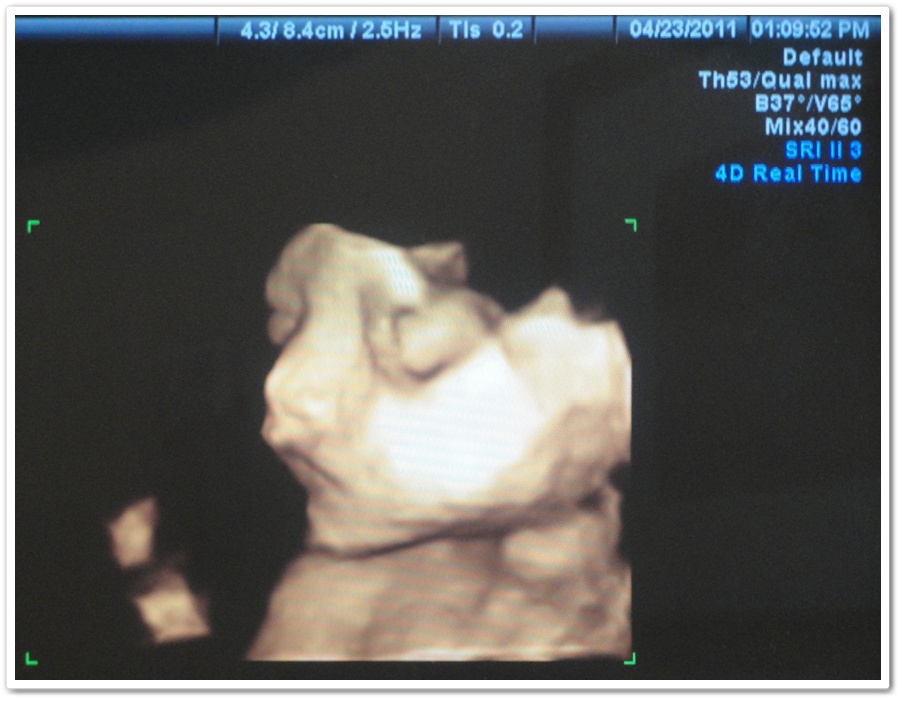

Trus abis itu baru dia ganti jadi 3D mode dan ngasih liat mukanya. Ada 3 foto yang diambil ama dia, ini yang paling lumayan keliatan menurut gua.

Yang keliatan banget ya dagunya panjang ya… turunan Esther banget. Hahaha. Andrew dagunya udah panjang, ini si Emma juga. Kok gak ada yang nurun dagu gua ya? 😛 Dulu pas USG 3D nya si Andrew yang keliatan tuh pipinya tembem banget (dulu emang pas bayi si Andrew tembem banget, sekarang aja jadi kurus), kalo si Emma ini gak gitu tembem ya keliatannya… Kayaknya jatohnya bakal lebih mirip ke Esther daripada gua dah… Gak apa deh biar cantik kayak mamanya ya… Hehehe. 😀